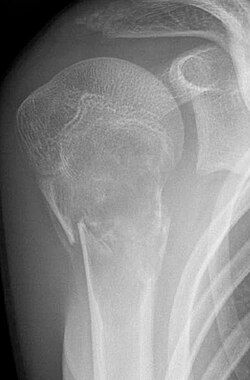

- Aneurysmatische Knochenzyste (AKZ): Gutartige, mehrkammerige Knochenläsion. Klassischer Befund in der MRT ist die „Spiegelbildung“ des Zysteninhaltes mit unterschiedlichen Signalintensitäten.

Aneurysmatische Knochenzyste im unteren Ende der Fibula bei 9-jährigem Mädchen. Kontrollaufnahme zwei Monate nach Kontinuitätsresektion und Überbrückung mit einem kortikospongiösen Span aus der Tibia (oben rechts). | Rüdiger Döhler: Lexikon orthopädische Chirurgie . Springer, Berlin 2003, ISBN 3-540-41317-0 , S. 9. | Surgeon and radiographer of the child | Datei:Aneurysmatische Knochenzyste.jpg | |